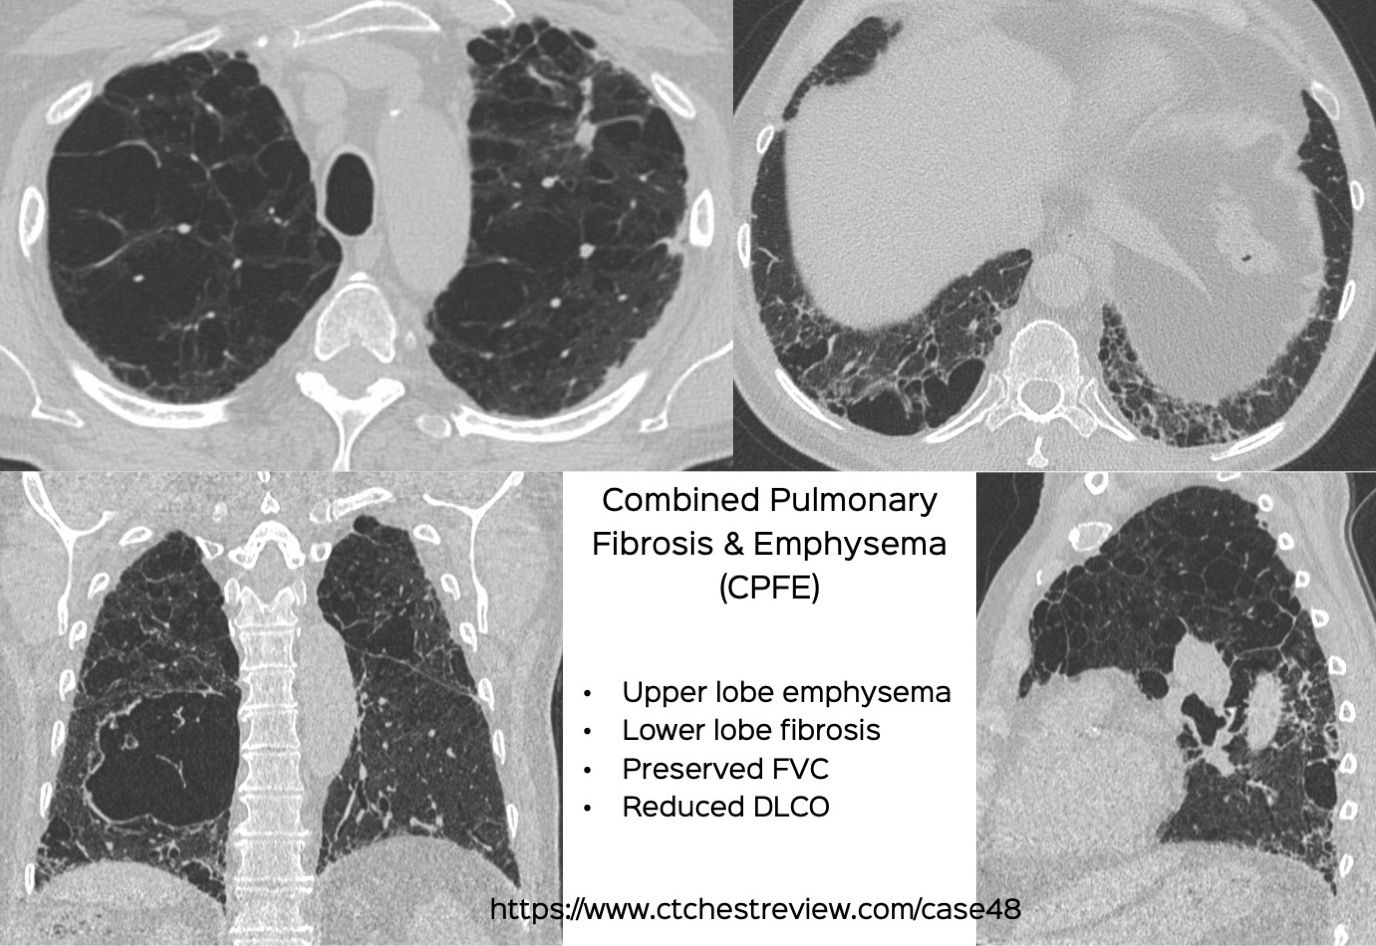

The official research statement on combined pulmonary fibrosis and emphysema (CPFE) was published last week. It has definitions to help us diagnose CPFE from a research perspective as well as clinically.

The video explains the salient features of the statement using a 69-years old 50-pack years smoker as an example.